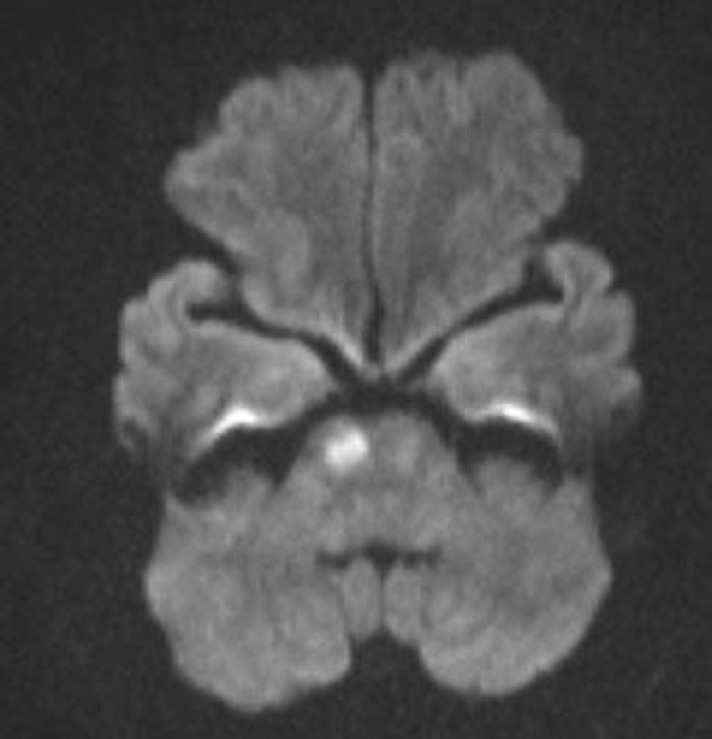

Hình ảnh Cộng hưởng từ sọ não (MRI) của người phụ nữ bị ong đốt: Với xung khuếch tán Diffusion cho kết quả nhồi máu cầu não phải (Ảnh: BVCC)

Vì vậy bệnh nhân được tiến hành chụp cộng hưởng từ sọ não ghi nhận nhồi máu cầu não phải. Người bệnh sau đó đã được xử trí tích cực và chuyển sang giai đoạn tập phục hồi chức năng tại Trung tâm Đột quỵ Phú Thọ.